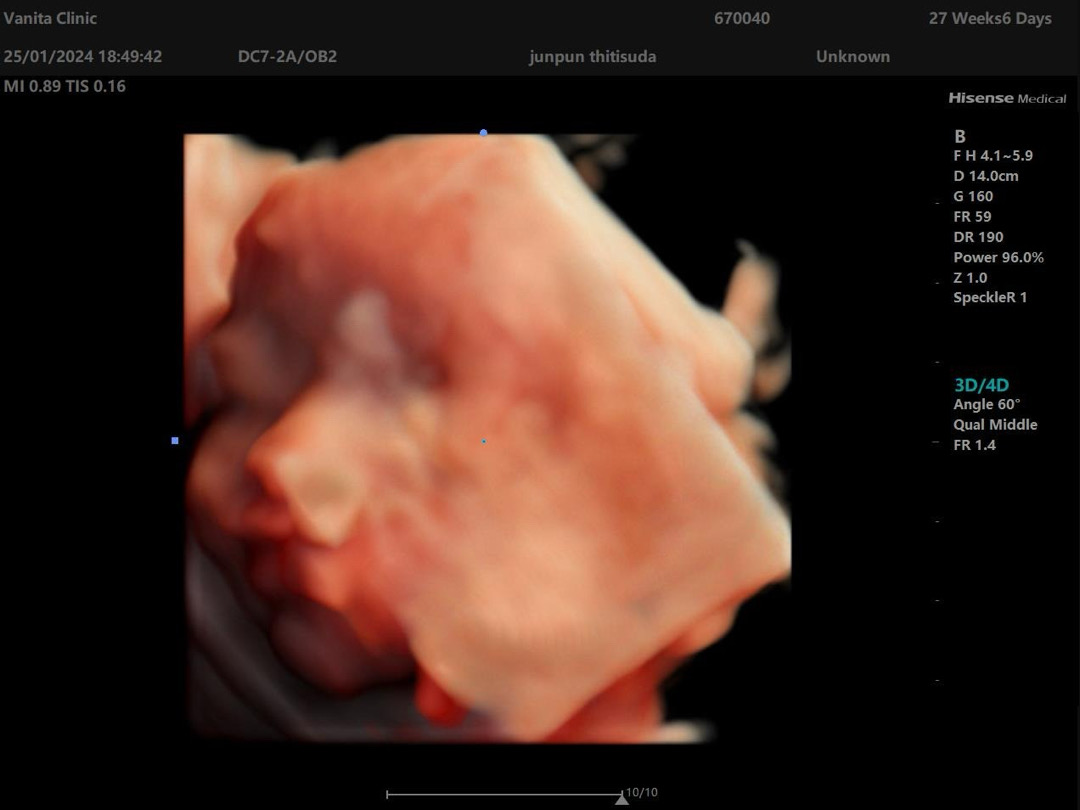

ด้วยความที่ภรรยาทานยาคุมกำเนิดที่แพทย์สั่งให้เป็นประจำอยู่แล้วเพราะเหตุผลทางโรคประจำตัว(ไม่เกี่ยวกับ Hb) เมื่อเรามีความพร้อม เราทั้งคู่ตัดสินใจมีเจ้าตัวเล็ก และภรรยาหยุดทานยาคุมชนิดอ่อนๆ และเราไม่ได้ตรวจหาความพร้อมก่อนมีบุตร เราและแฟนมีภูมิลำเนาเดิมในภาคตะวันออกเฉียงเหนือ ซึ่งเป็นพื้นที่ที่คนเป็น E-Trait ค่อนข้างเยอะ(อ้างอิงแพทย์ จุฬาฯ) เมื่อตั้งครรภ์เข้าเดือนที่ 2 คุณหมอให้คุณแม่ตรวจ Hb typing ปรากฏว่าเป็น E-Trait ไม่รอช้า คุณหมอให้คุณพ่อตรวจด้วย ตอนนั้นใจตกอยู่ตาตุ่ม กลัว และกังวลมาก กลัวลูกจะเป็นอะไร และด้วยความเราเรียนวิทย์-คณิตมาโดยตรงเรามีความเข้าใจดีว่าเปอร์เซ็นต์การเกิด E Hb มีกี่ % ผลตรวจออกมาพ่อก็เป็น E-Trait ตอนนั้นใจอยู่ไม่สุขละ ปรึกษาเพื่อนที่เป็น Med. Tech. เอย หมอเอย เพื่อนๆผู้มีประสบการณ์ ดูคลิปคุณหมอมาบรรยายในยูทูปเอย ก็ทำให้เราสบายใจขึ้นมาบ้าง มาถึงเดือนที่ต้องตรวจความผิดปกติ คุณหมอเด็กได้ u/s อย่างละเอียด ผลคือ ลูกชายผมปกติดีไม่มีความพิการใดๆ แต่ก็ไม่อาจรู้ได้ถึงโรคทางพันธุกรรม ซึ่งต้องเจาะน้ำคร่ำหรือรอตรวจเลือดตอนคลอด ผมเลือกที่จะไม่เจาะเพราะ complicated ค่อนข้างเยอะ ณ วันที่เขียนบรรยายนี้ ลูกชายผมอยู่ในครรภ์คุณแม่ 31+3 weeks แล้ว ตัวโต ดิ้นดีมาก ทุกคนเป็นกำลังใจและภาวนาให้ลูกชายผมปกติไม่เป็นธารัสซีเมียหรือพาหะใดใดด้วยนะครับ 🙏🏻 เจอกันเดือนเมษายน 2567 นะลูกชาย ✌️ ปล. ลูกคนที่ 2 อาจจะต้องให้คุณหมอเข้าช่วยเหลือแล้วครับ ใครที่กำลังแพลนจะมีบุตร เช๊คด้วยน้าา สำคัญสุด! #เล่าเรื่องลุ้นรางวัล #ทีมปีมังกร